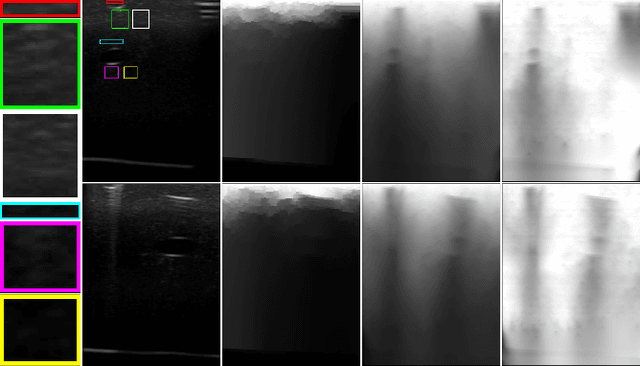

Abstract:Ultrasound imaging has been improving, but continues to suffer from inherent artifacts that are challenging to model, such as attenuation, shadowing, diffraction, speckle, etc. These artifacts can potentially confuse image analysis algorithms unless an attempt is made to assess the certainty of individual pixel values. Our novel confidence algorithms analyze pixel values using a directed acyclic graph based on acoustic physical properties of ultrasound imaging. We demonstrate unique capabilities of our approach and compare it against previous confidence-measurement algorithms for shadow-detection and image-compounding tasks.